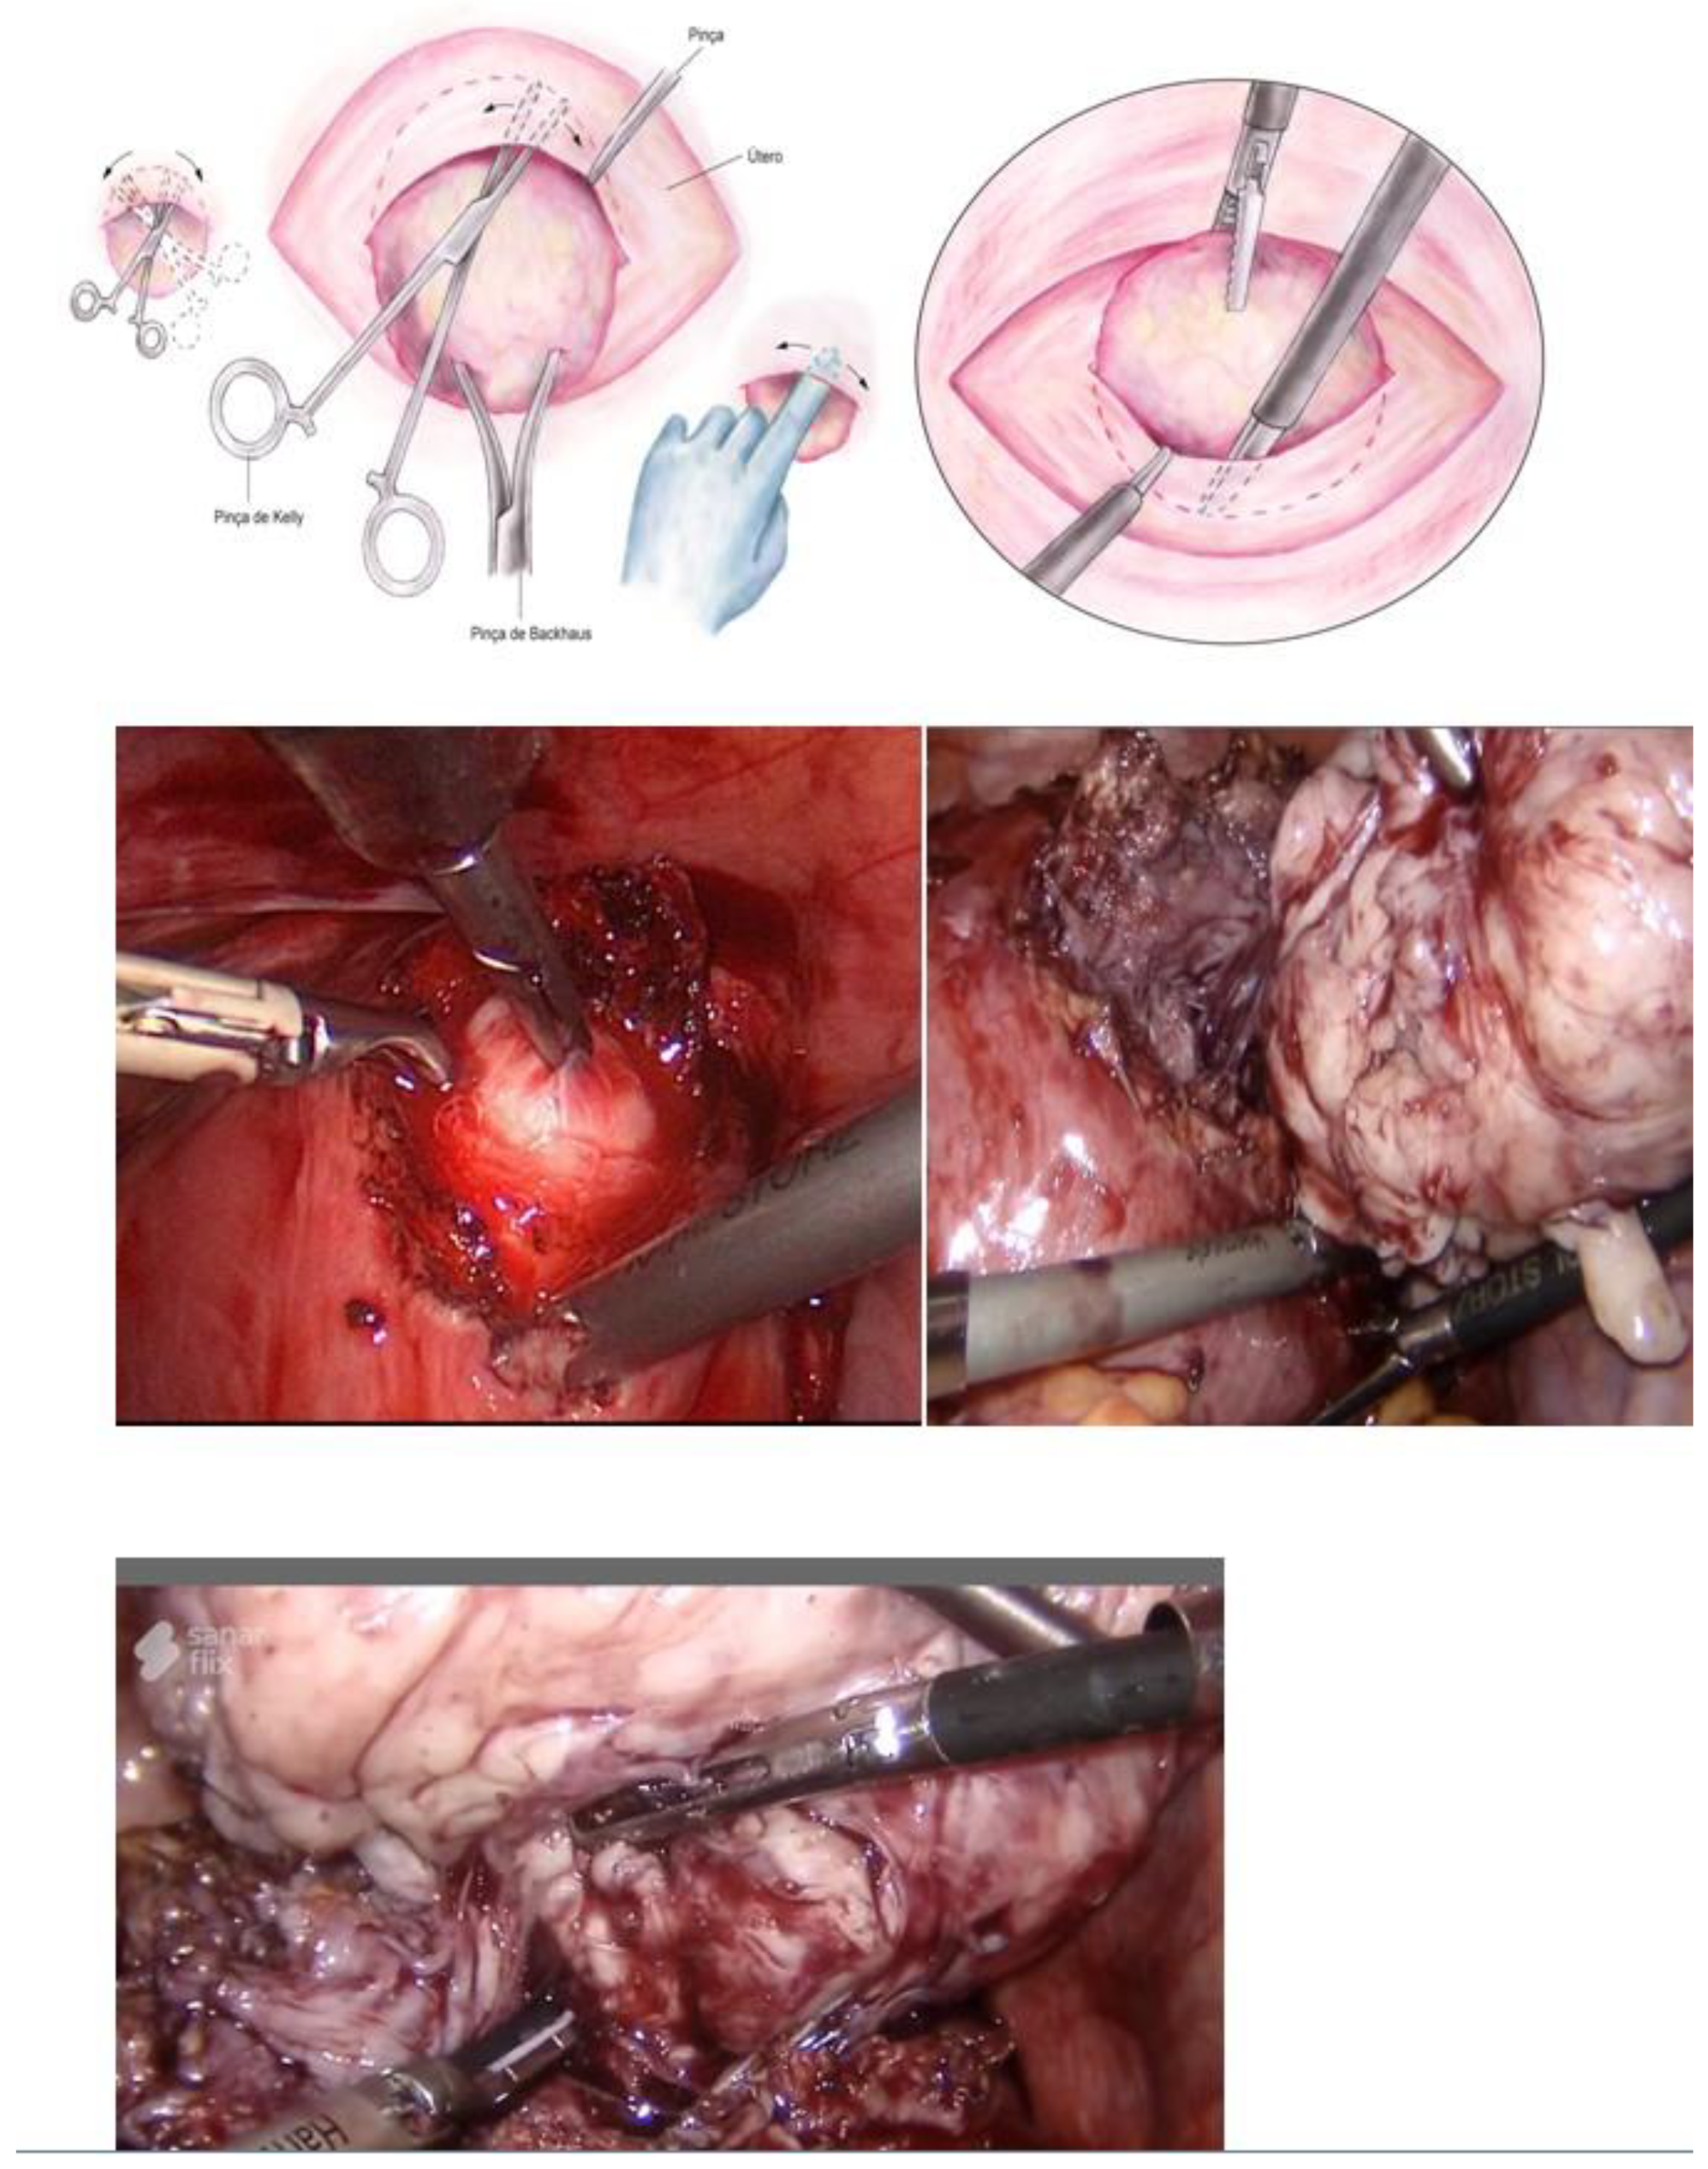

Hysteroscopy, as a method of direct visualization of the uterine cavity, offers all possible information about the intracavitary portion of the submucous myoma and a good assessment of the portion of the myoma, which is found in the myometrium, intramural portion. Thus, with hysteroscopy, it is possible to classify the submucous myoma and assess the need for other imaging methods. Another important function of hysteroscopy is to rule out other intrauterine causes of bleeding and to carry out an anatomopathological study of the endometrium or of the identified lesions, so it should, whenever possible, be indicated in the investigation (Figure 1).

Figure 1. Submucous myoma—hysteroscopic view.